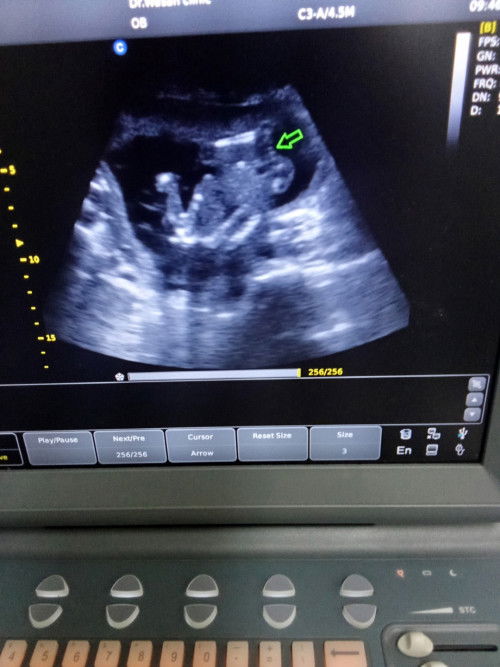

แม่ๆ ช่วยดูหน่อยได้ไหมคะะ แบบนี้เพศหญิงหรือชายคะ ซาวด์ตอนสี่เดือนหมอบอกเป็นหญิง กลัวย้ายทีมมากค่ะ หมอบอกว่ามีกรีบ

แล้วของเราเป็นกลีบชัดมากค่ะ แต่หมอยังไม่คอนเฟิร์มว่าเพศอะไร